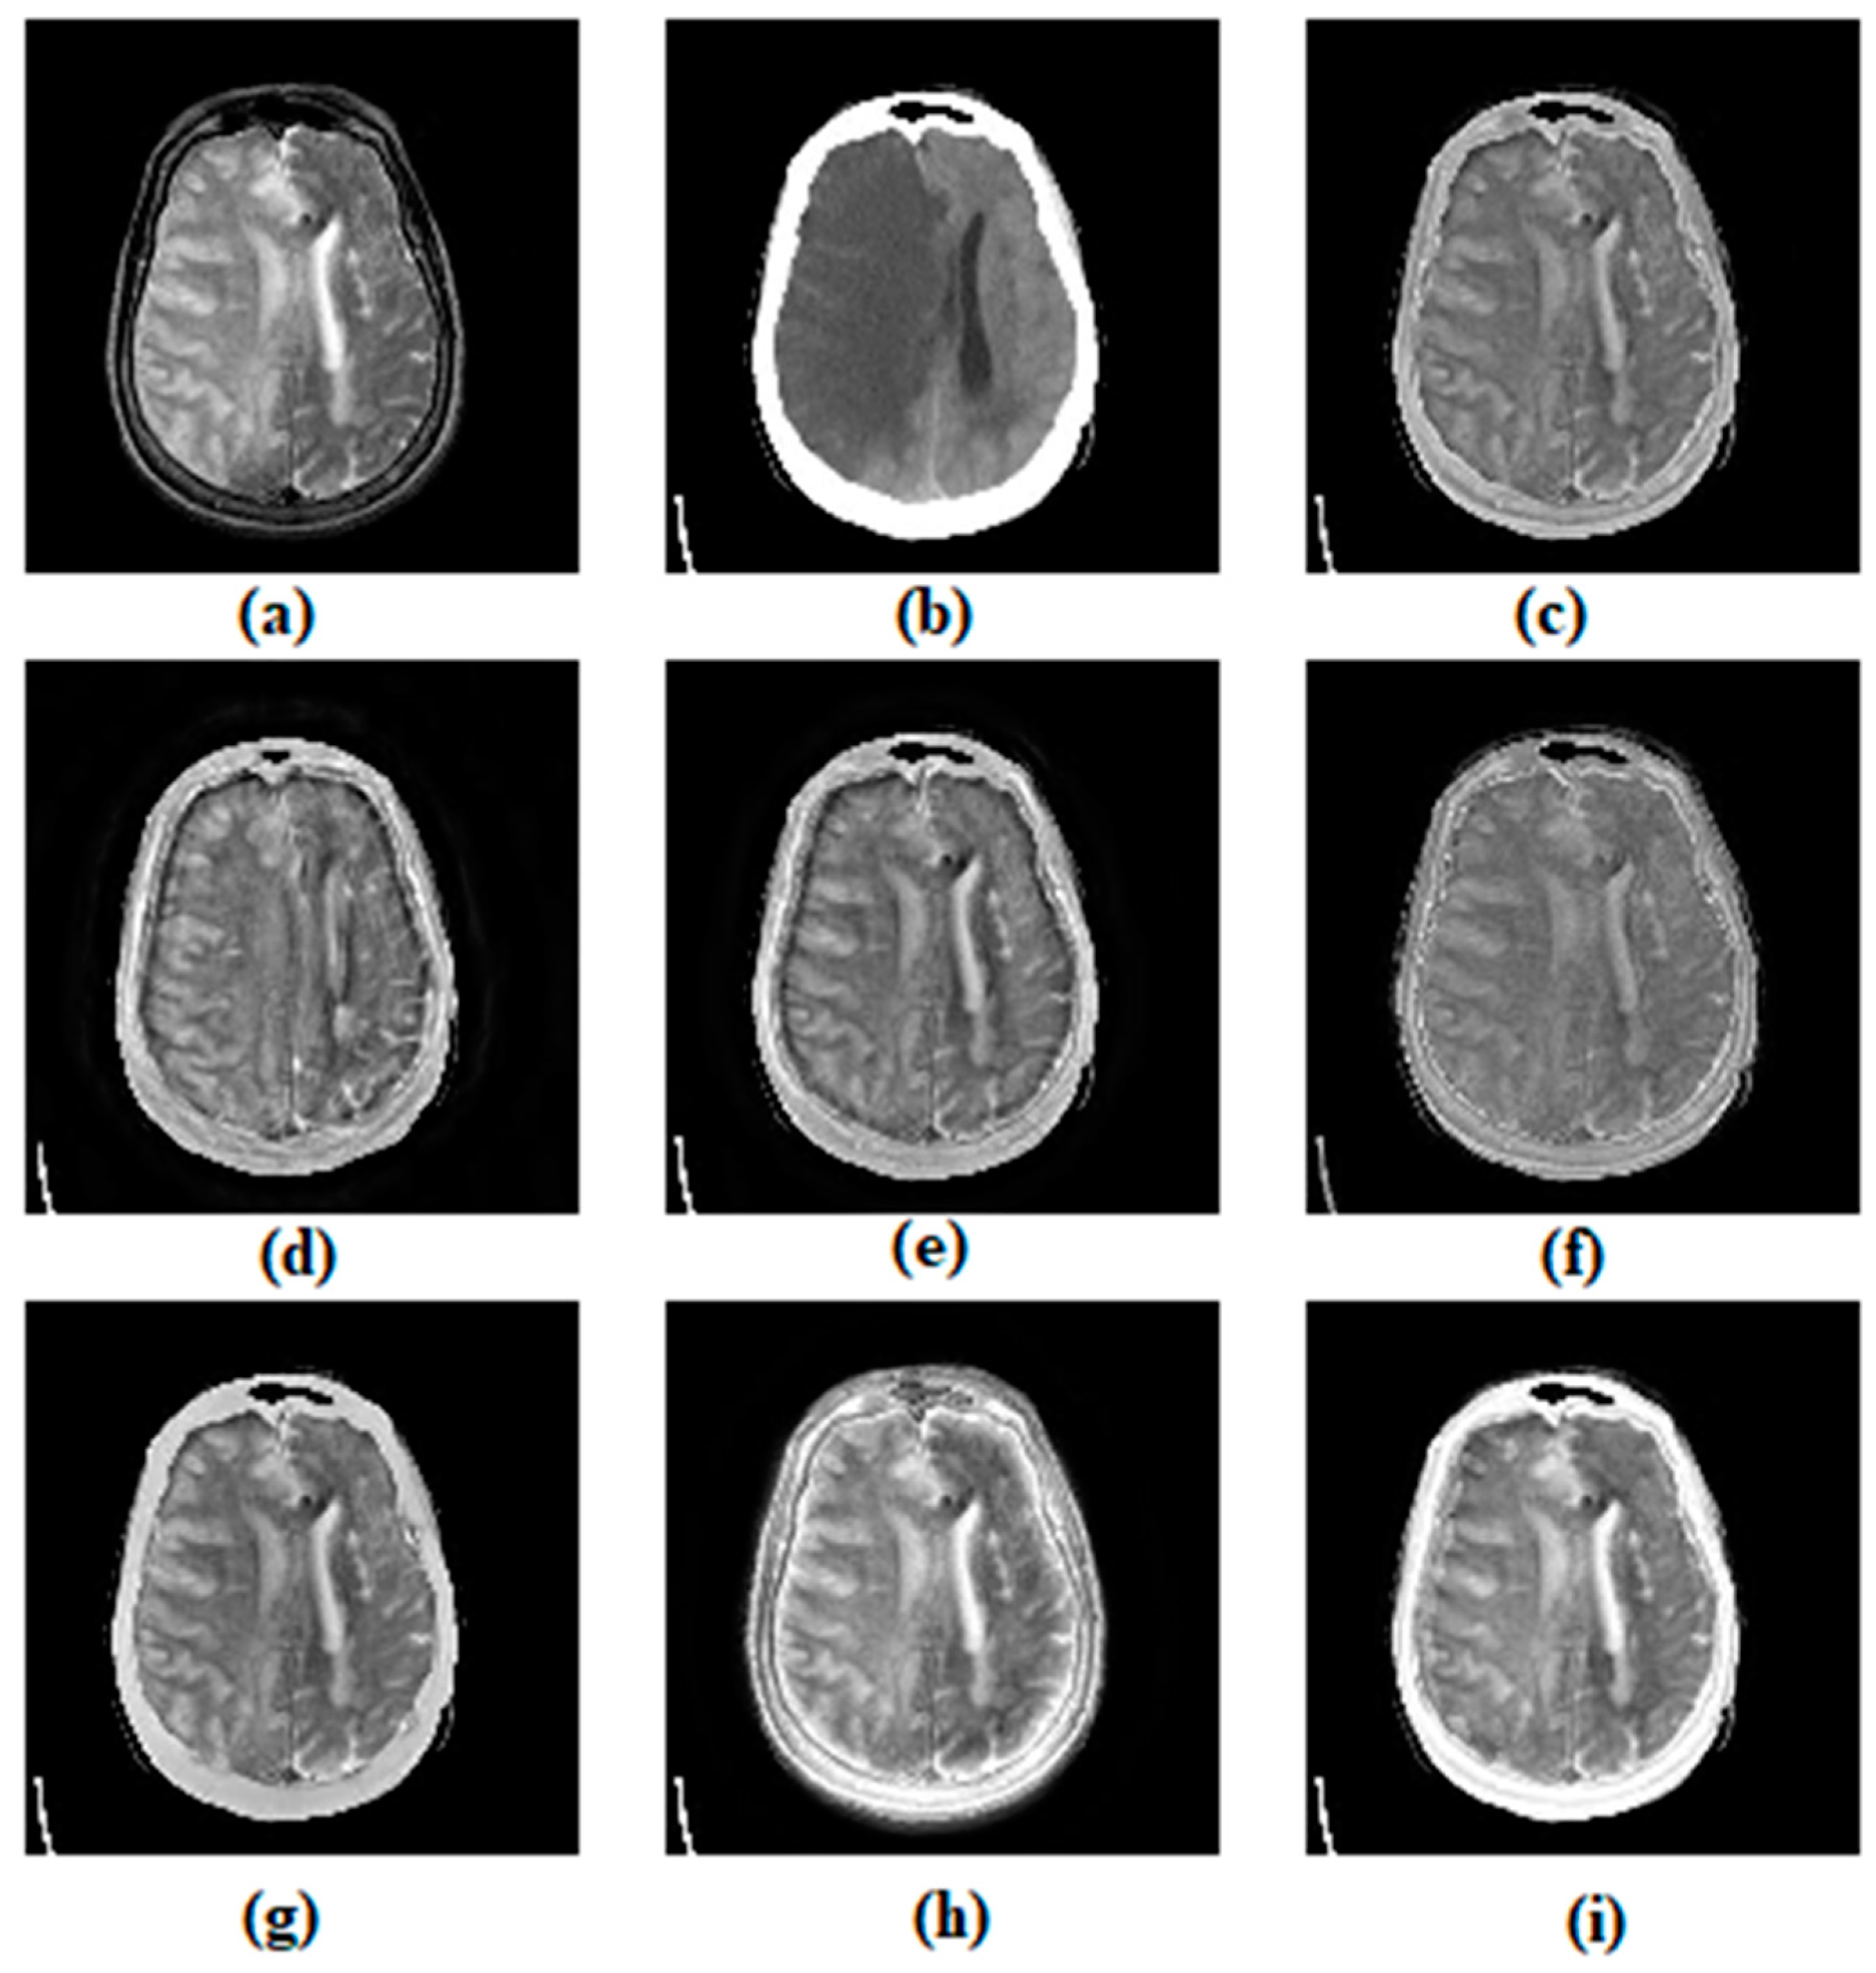

3.1. Subjective Assessment